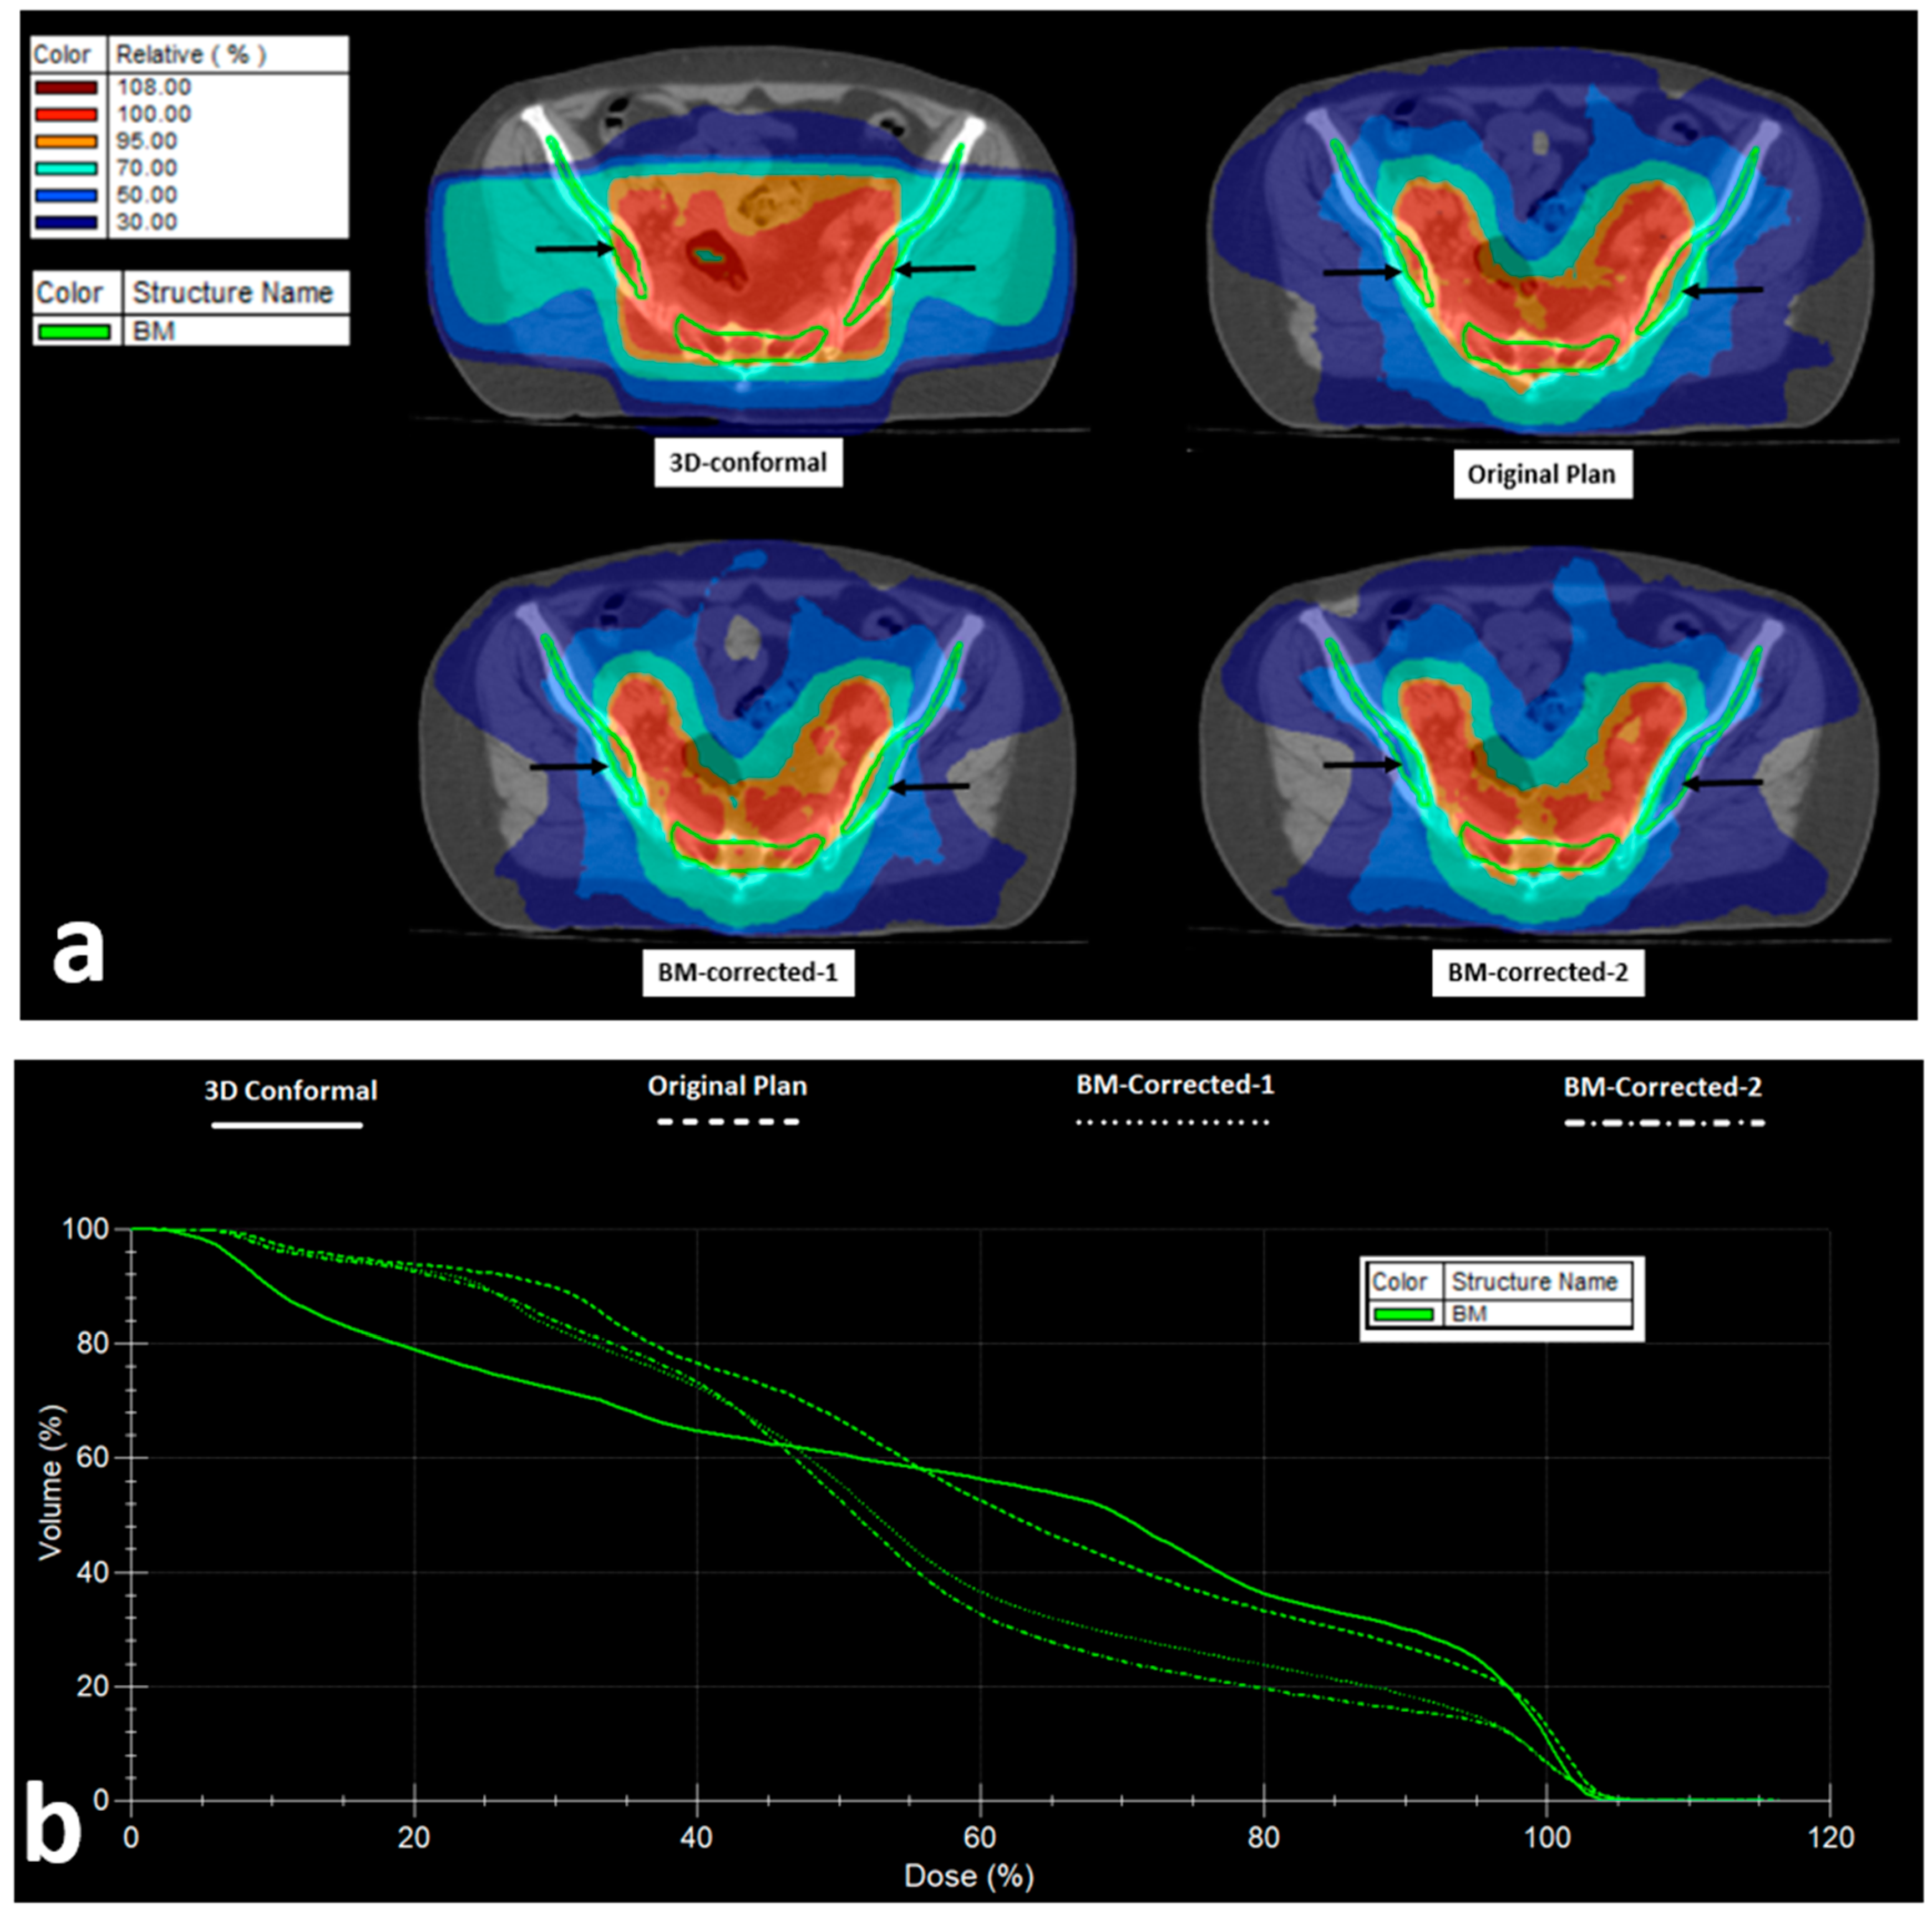

Figure 5 shows isodose distribution and DVH of the BM of the 3D-conformal, original VMAT, and the BM-corrected-1 and -2 plans.

Figure 5.

VMAT Radiotherapy planning and bone marrow (BM) dose distribution: (a) Isodose areas distribution in 3D-conformal, VMAT (original), and VMAT plans taking into account the bone-marrow as an organ at risk (BM-corrected-1), and VMAT with PTV correction to exclude the BM from iliac and ischium bones (BM-corrected-2) (black arrows show the iliac BM area). (b) Dose–volume histograms of the bone marrow in the four abovementioned RT plans.